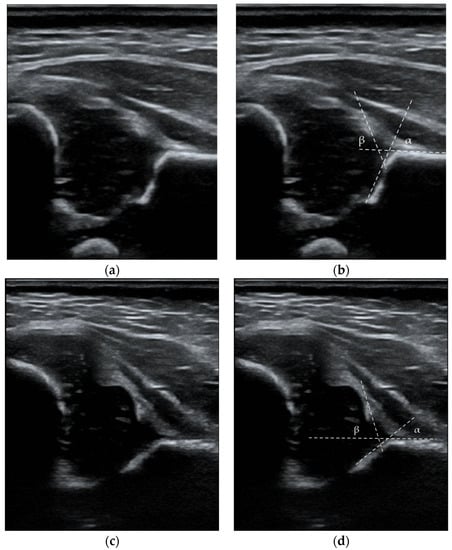

According to Graf’s classification, the diagnostic criteria for DDH were type IIa (-), IIb, IIc, D, III, and IV images. Type IIa hips before 6 weeks of age were monitored and treated only in the absence of signs of sufficient maturation (IIa (-) or IIb) []. Figure 2 presents ultrasound images from the data set with the measurements outlined. Our clinic recommends the first ultrasound examination at 6 weeks of life. In the case of a positive physical examination at birth or risk factors, ultrasound is recommended in the first weeks of life. The second control visit is also recommended for healthy children at 12 weeks. The history of hip orthopedic examination included the maximum abduction angle value for each hip joint, the Ortolani test, the Barlow test, and the Galeazzi test. The abduction asymmetry was defined as a difference of 20° or more. Articular noises on physical examination such as “clicks” or “creaks” were not classified as pathological findings []. The record included the name, national identification code, age, and date of visit. Information on possible risk factors such as female sex, abnormal presentation, high birth weight, term of birth, MuP, mode of delivery, diabetes, positive family history and coexisting medical conditions in children was collected.

Figure 2.

Ultrasound images with the measurements outlined: (a,b) Type IB, hip joint according to Graf, α = 68° β = 67°; (c,d) Type III, hip joint according to Graf, α = 42° β = 73°. White lines represent the base line, the bony roof line, and the cartilaginous roof line.